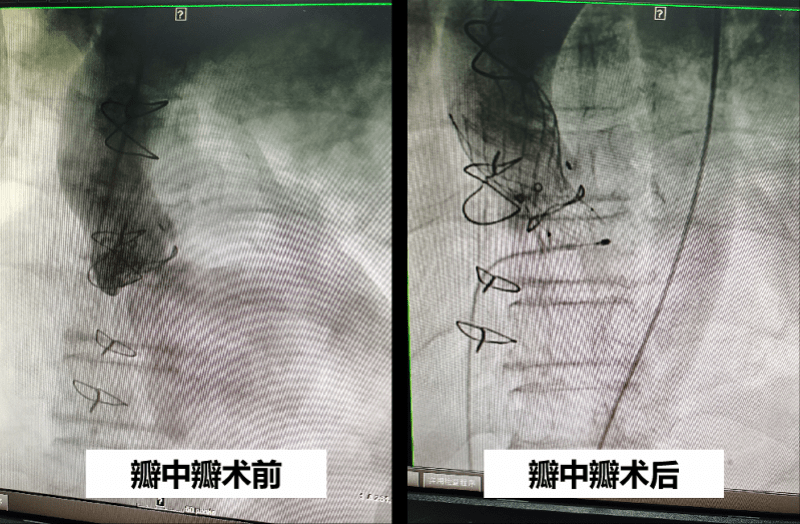

患者接受手术前后检查结果对比

以前出现生物瓣膜衰败 , 只能通过再次开胸手术解决 , 并且需要在心脏停止跳动下完成 。 随着介入瓣膜技术的发展 , 经导管瓣膜植入术(TAVR)——也被称为“瓣中瓣”技术——可以实现在原先衰败的瓣膜中间通过介入的办法放进去一个新的瓣膜 , 而不用正中开胸把原先的瓣膜取出 , 并且心脏无须停止跳动 , 极大地缩短了手术时间和风险 。